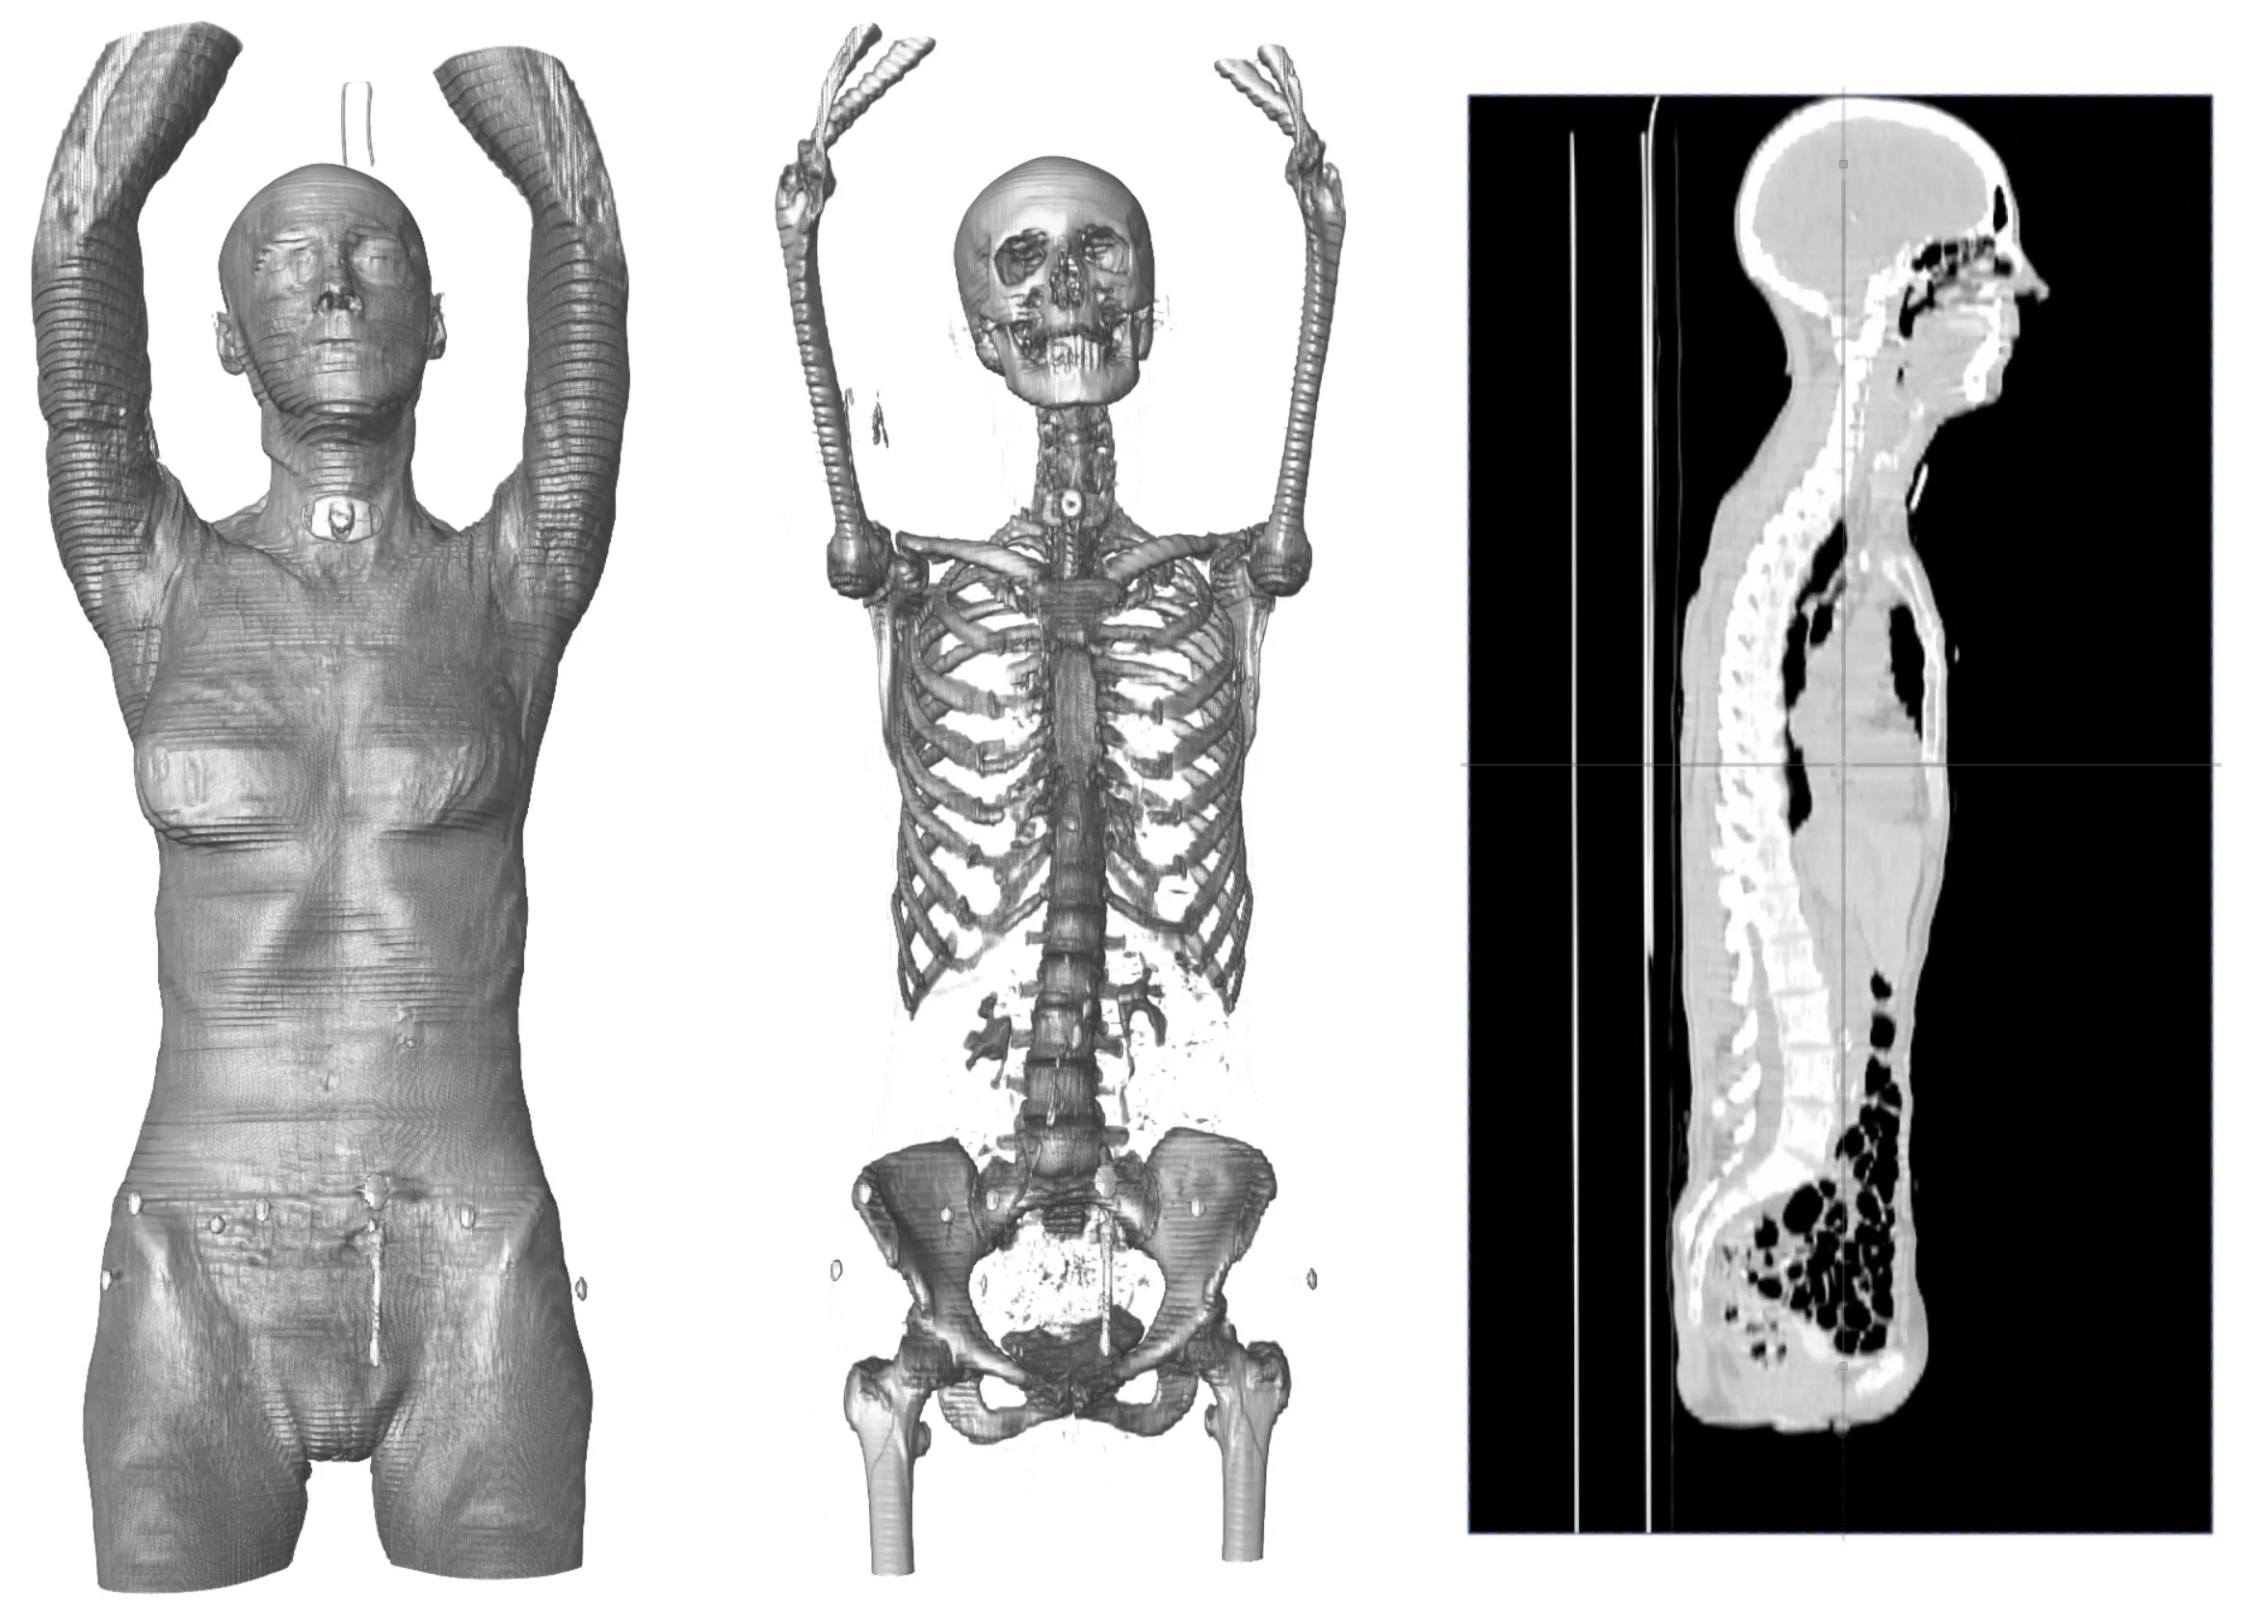

Load Volume & Surface Data

Load DICOM scans (DCM files), PLY, STL, OBJ, and WRL surfaces. Extract multiple isosurfaces from volume (DICOM) scans (and export them).

View and Interact in 3D

Interact with your scans through 3D multi-planar reconstruction and axial, coronal, and sagittal slicing. View through 3D volume rendering and slice-surface intersections.